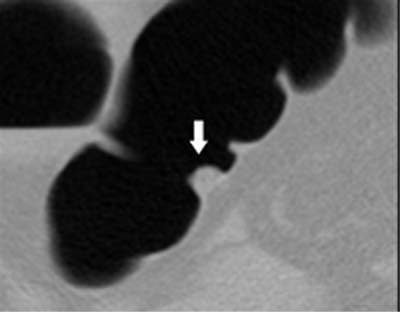

| Above, soft-tissue filling defect in the lateral rectum. Straight line in the axial CT image at left represent CAD detection. Arrow in image at right indicates the same defect in the coronal view. From Fletcher JG, Summers RM, Johnson CD, MacCarty RL, Wilson LA. Lessons in Detection: Contribution of Computer-aided Detection with Perceptively Challenging Lesions at CT Colonography. Supplement to Radiology November 2002, Vol. 225, p. 304. RSNA December 1-6, 2002, Chicago. Image courtesy of Dr. Joel Fletcher, © Mayo Medical Foundation, 2002. |